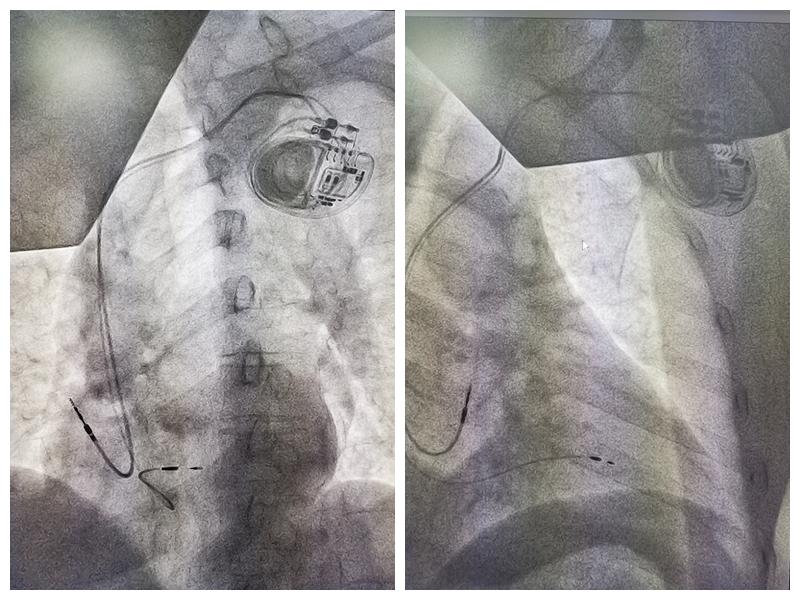

2月19日,当大家还沉浸在新年的悠闲自在中时,湘西州人民医院心内三科已经投入到了紧锣密鼓的手术中,并成功完成湘西地区首例3T MRI兼容双腔起搏器植入。

心内三科起搏与电生理团队经过术前缜密讨论,患者有安装永久起搏器指征,由于患者基础疾病多,考虑到未来患有其它疾病需要进行MRI检查诊断的需求较高,建议患者选择MRI兼容起搏器。医生团队通过与患者和家属进行充分沟通后,患者选择了3T&1.5T MRI全身无限制兼容起搏器(X3DR01)。

心内三科主任彭学军介绍:X3DR01是国内首个3T MRI兼容的经静脉起搏器,打破了以往植入起搏器患者只能接受1.5T MRI检查甚至不能接受MRI检查的局限,让患者可以自由选择3T MRI或者1.5T MRI扫描,从而拥有了享受更优质医疗资源的机会,也打消了患者和医生在植入器械上的后顾之忧,除了独有3T MRI兼容外,X3DR01采用全新硬件平台,优化电路结构,大幅降低系统能耗,从而能够提供超强的电池续航动能,超长的使用寿命也让患者减少更换次数,降低感染风险。